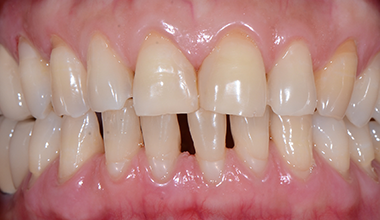

심미보철 CASE

치료 전 -

치료 후

다이아스테마 - 앞니 벌어짐